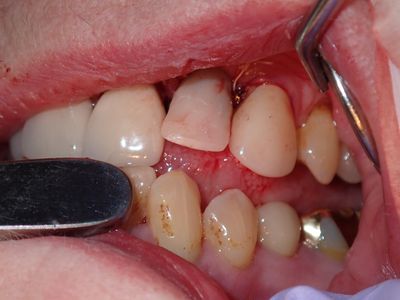

long root, atraumatic exo, loss of labial bone at apical end of socket, implant placed in ideal position, socket and buccal grafted with allograft and collagen membrane. Sutured prior to loading implant with screw-retained temp crown out of centric and protrusive occlusion

PA180024.JPG